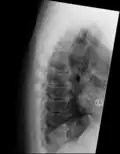

Confluent ossification of multiple contiguous vertebral bodies in diffuse idiopathic skeletal hyperostosis (DISH) -